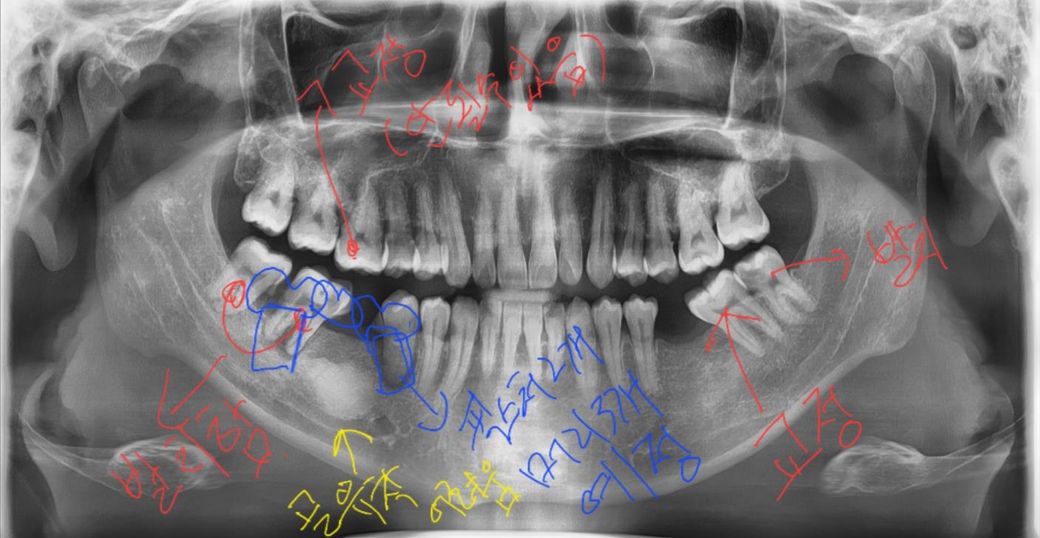

임플란트 때문에 여기저기 문의한 치과가 많은데 치료방법이 병원 마다 달라서 어떻게 해야될찌 몰라서 지식인에 올려봅니다

1. 사진상 왼쪽위 쳐진 어금니를 부분교정하려고하는데 치과에서 안될수도 있다고 하네요 교정이 안될경우 교합때문에 치아를깍아내거나 신경치료 및 크라운을 해야한다고 하는데 부분교정이 어려울 까요? 그리고 부분교정이 안되었을 경우 치아삭제를 할때 가장 좋은 방법은 무엇인지 궁금합니다.

2. 사진상 왼쪽 아래 염증이 있는 치아는 두개다 발치를 한 상태입니다. 임플란트 픽스처를 2개만 권하는데도 있고 3개를 권하는 병원도 있어 어느게 좋은지 궁금합니다 2개를 권하는 병원은 가운데 골밀도가 높은곳은 픽스처 골유착이 잘안될꺼 같다고 말씀하시는데 어떤 치료방법이 장기적으로 좋은 치료방법인지 궁금합니다

3. 사진상 오른쪽 쓰러져있는 어금니를 부분교정할 예정입니다 뒤쪽 충치가있는 사랑니는 발치예정입니다

문제는 쓰러져있는 어금니를 4달 전에 충치가있어 레진치료를 받았는데 딱딱한걸 씹거나 차갑고 뜨거운걸 먹을때 찌릿하고 묵직한 통증이 있다는 겁니다 충치가있는 사랑니를 발치하고 쓰러진 어금니를 치료후 교정하는게 좋은지 교정후 치료하는게 좋은지 그리고 저상태에서 신경치료 없이 크라운 치료가 가능한지 궁금합니다

1. 치아가 정출이 되서 추후 보철물 제작시 공간 확보를 위해서 크라운 치료를 하셔야될것같습니다.

2. 양쪽에 임플란트를 2개 심고 브릿지 치료를 하시면될것같습니다.

3. 교정을 하셔서 공간확보후에 임플란트를 하셔도 되고 치료를 빨리 끝내고 싶다면 크라운 치료를 하시는게 좋을것같습니다.

1. 저정도 압하 부분교정은 크게 어렵지 않을 것 같습니다 아마 부분교정으로 해결될 것 같으나 안되면 치아 높이 낮추고 시릴 수 있으니 크라운 씌우면 됩니다

2. idiopathic sclerosis 상태로 골유착 문제보다는 심는거 자체, 재료선택이 좀 까다로울 수 있습니다 심기만 하면 골유착은 잘 될 것 같습니다 다만 저런 상태가 아니었다 하더라도 2개심고 브릿지 연결하는 치료계획 나쁘지 않습니다

3. 상기 증상으로 봐서는 신경치료 필요할 것 같습니다